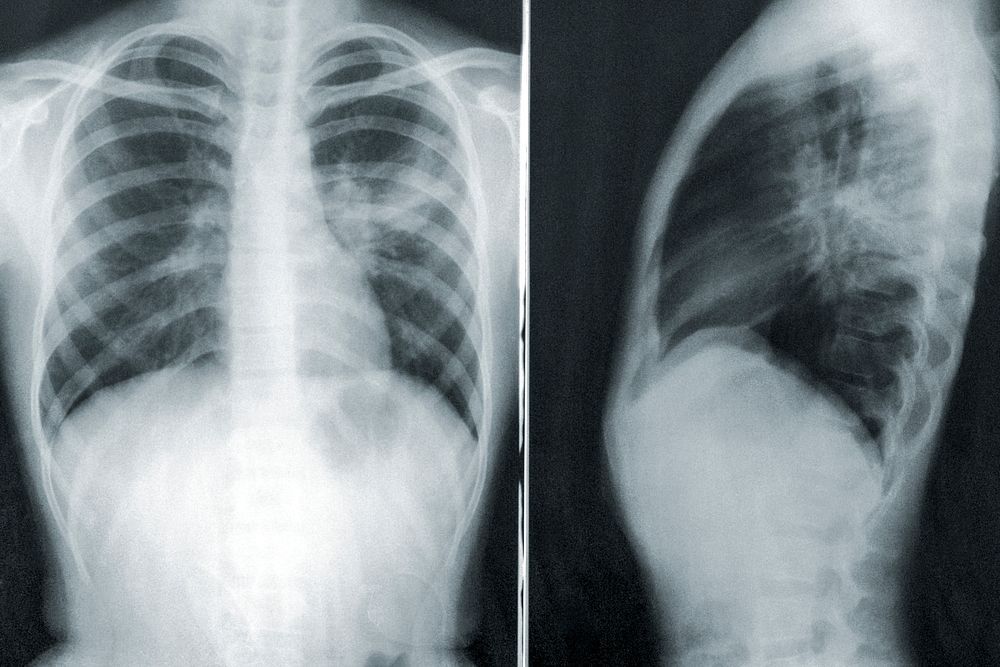

भारत की तपेदिक के खिलाफ बढ़ती कामयाबी: WHO ग्लोबल टीबी रिपोर्ट 2024 में भारत की प्रगति को मिली सराहना

विश्व स्वास्थ्य संगठन (WHO) द्वारा 29 अक्टूबर 2024 को जारी की गई ग्लोबल टीबी रिपोर्ट 2024 में भारत की तपेदिक (टीबी) के मामलों की पहचान और उपचार में तेजी से हुई प्रगति की सराहना की गई है। रिपोर्ट के अनुसार, भारत ने 2015 से टीबी मामलों की पहचान के अंतर को तेजी से कम किया है, जिससे देश की उपचार कवरेज में बड़ा सुधार हुआ है।